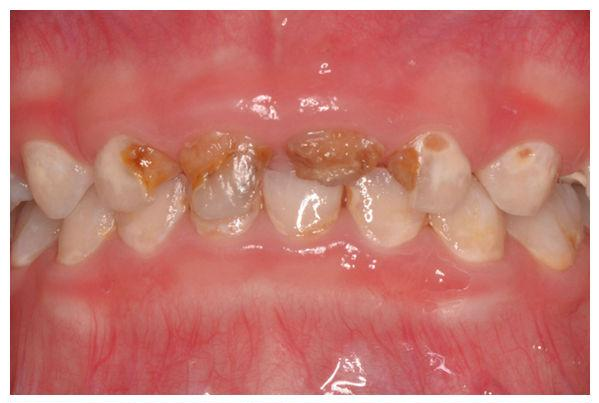

兒童齲齒治療